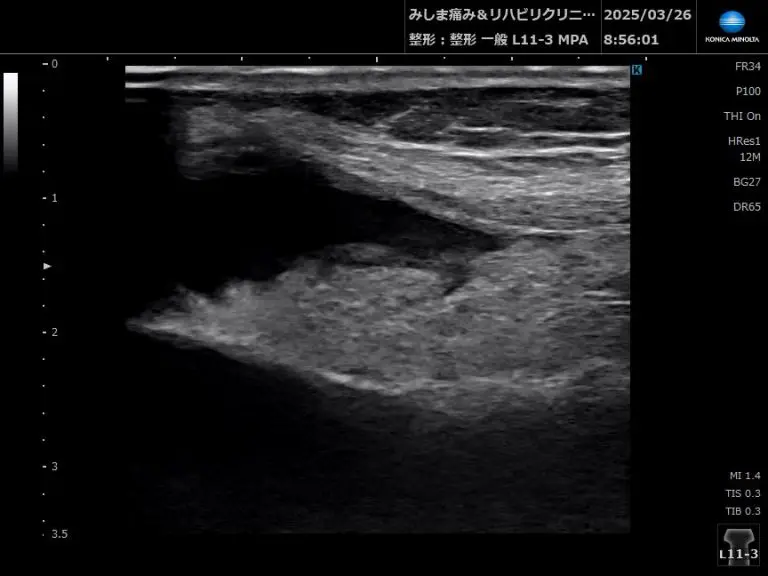

- **関節内液(関節水腫)**の確認

→ 滑膜炎や感染、外傷後の炎症などで関節液が貯留します。

→ 関節腔が広がり、低エコー域(黒っぽい)が認められます。

膝の膝蓋上納への水腫